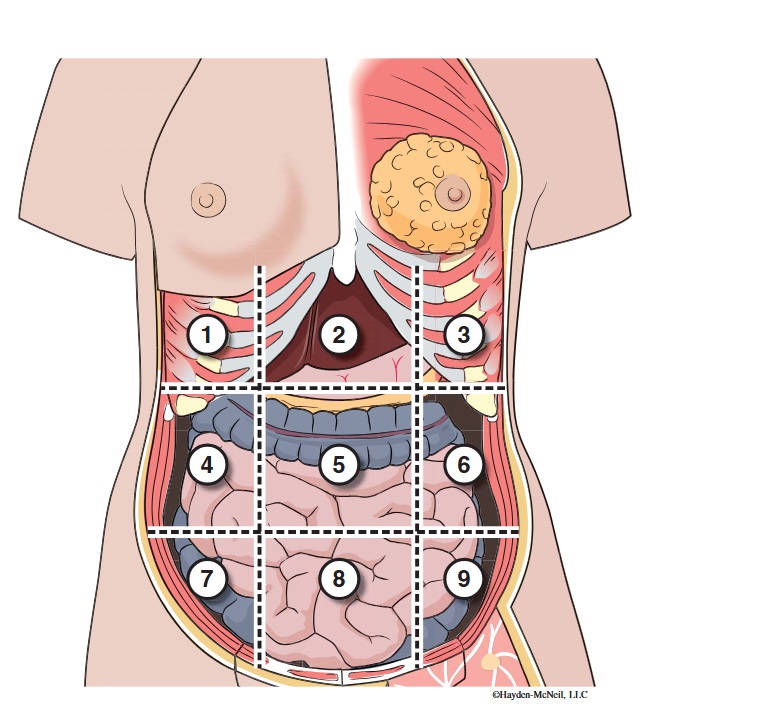

What abdominal region is labeled #1?

right hypochondriac

What abdominal region is labeled #2?

epigastric

What abdominal region is labeled #3?

left hypochondriac

What abdominal region is labeled #4?

right lumbar

What abdominal region is labeled #5?

umbilical

What abdominal region is labeled #6?

left lumbar

What abdominal region is labeled #7?

right iliac/ inguinal

What abdominal region is labeled #8?

hypogastric

What abdominal region is labeled #9?

left illiac/ inguinal

What organs are apart of the right hypochrondriac region?

right lobe of liver, gallbladder, right adrenal gland

What organs are apart of the epigastric region?

pyloric end of stomach, duodenum, pancreas

What organs are apart of the left hypochondriac region?

stomach, spleen, left adrenal gland

What organs are apart of the right lumbar region?

ascending colon, right kidney, portion of small intestine

What organs are apart of the umbilical region?

omentum, mesentery, small intestine

What organs are apart of the left lumbar region?

descending colon, left kidney, portion of the small intestine

What organs are apart of the right iliac/ inguinal region?

cecum of large intestines, appendix, right ovary

What organs are apart of the hypogastric region?

ileum, bladder, uterus

What organs are apart of the left iliac/ inguinal region?

sigmoid colon, left ureter, left ovary